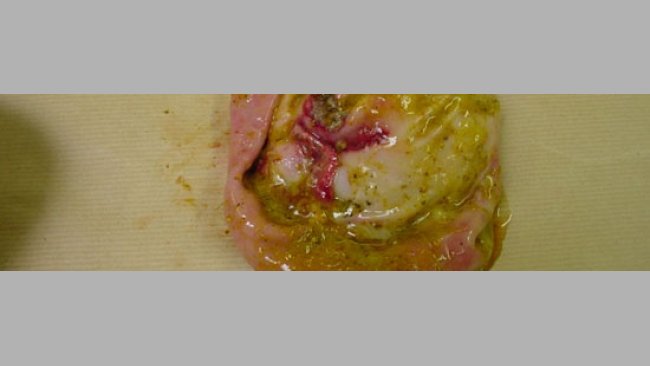

Con los análisis en la mano, se visita de nuevo la explotación para atender dos muertes más, pero esta vez de dos lechones, uno de ellos con 5 semanas de vida, y otro con una semana de entrada en cebo. Ambos mueren en el mismo momento, y cuando se observan los cadáveres, el animal mayor presenta también una coloración abdominal intensa oscura, así como parte de las orejas. El pequeño muestra una pequeña zona coloreada, pero presenta también un mayor grado de timpanización.

El primer germen en que se pensó fue E.coli, el cual se encontró en varias explotaciones, provocando muertes en cebo, pero en estos casos los hallazgos en las necropsias fueron muy claros, con presencia de paredes gástricas engrosadas y exudado fibrinoso en el intestino, de color amarillento claro. En los cerdos no aparecían signos de este tipo, por lo que no se sospechó, al menos como agente principal, de E. coli.

Otro agente suficientemente patógeno como para producir muertes rápidas, y con síntomas externos que recordaban a una septicemia, eran las Salmonellas, por lo que en el segundo análisis pedimos una investigación de este germen, obteniéndose un resultado positivo.